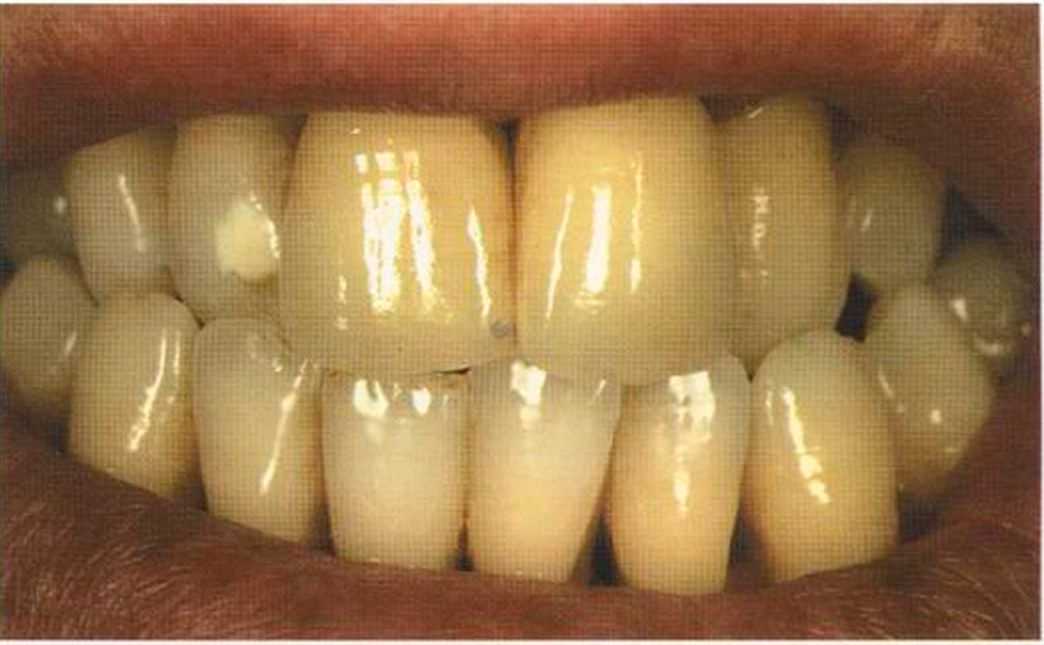

Эта женщина пришла в клинику доктора Лангханке с металлокерамической реставрацией.

Ей не нравились типичные в таких случаях темные края коронок и опаковость керамики.

Цвет 1М1 до 1М2 основной цвет в данном случае.

Часто эти валики можно увидеть лишь под определегшым углом. Важно осмотреть работу со всех сторон. Поворот и наклон зуба затрудняют соблюдение и контроль этого

«правила отражения валиков».

Отмечаем, что десна здоровая. Она гармонирует с коронкой ln-Сегат за счет отличных свойств материала

и отличного краевого прилегания.

Теперь коронки в области боковой группы зубов не нравятся, и в скором времени их тоже будем переделывать.

Коронки выполнялись в моей лаборатории вместе с пациентом. Мы работали долгих четыре часа, чтобы всем понравился результат. Обратите внимание на отражение света по краевым валикам. Мезиальные валики коронки 12 зуба гармонично переходят в дистальные валики 42 зуба. В идеальном варианте «отражающиеся валики» должны проходить по прямой линии. Это привило для всех мезиальных и дистальных валиков фронтальной группы зубов. Оно имеет очень важное значение и влияет на результат нашей работы.

Эти валики проходят перемещаясь, однако по одной линии. Примером здесь являются мезиальные поверхности на коронке 11 и на 31.